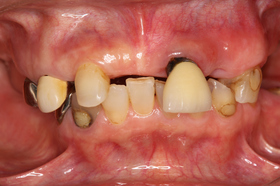

下の写真の患者さんも上下に部分義歯を装着しておりましたが、噛み合わせの不良により前歯部に負担がかかり、前歯が歯根破折により抜歯せざるをえない状態でした。

また、残存している天然歯も著しく摩耗していたり、病的に移動していたりします。

見た目においても、天然歯に被せてあるクラウンと義歯の調和はとれておらず、患者さんもとても気にされておりました。

治療は、装着されている不適合クラウンはすべて除去して仮歯にし、虫歯治療や根管治療を行いました。

また、欠損部には治療用の義歯を作製して、噛み合わせ・見た目・最終的な義歯形態などについて検討しながら治療を進めていきました。